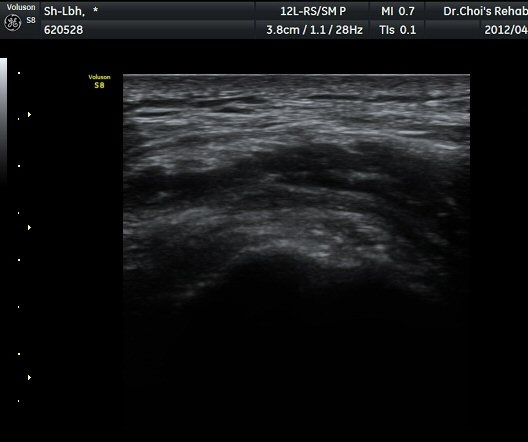

ÃÊÀ½ÆÄ °Ë»ç

´ëÀüÀÚ(gtreater trochanter) ¾ÕºÎºÐ Ⱦ´Ü¸é °Ë»ç¿¡¼­ ´ëÀüÀÚ Ç¥Ãþ¿¡ ¼ÒµÐ±ÙÀÌ °í¿¡ÄÚ ¼¶À¯¾ç ¸ð¾çÀ¸·Î °üÂûµÇ°í ¼ÒµÐ±Ù°ú Àå°æÀÎ´ë »çÀÌ¿¡ ¾à 2mm µÎ²²ÀÇ Á¤¾×³¶ ºÎÁ¾ÀÌ °üÂûµÈ´Ù(±×¸² 1, ³ë¶õ»ö È­»ìÇ¥) . ŽÃËÀÚ¸¦ µÚÂÊÀ¸·Î À̵¿ÇÏ¿© Áߵб٠ÈûÁÙÀÌ °üÂûµÇ°í Áߵб٠ÈûÁÙ ºÎÂøºÎ ÀϺο¡ ¹«¿¡ÄÚ ¿¬°á¼º ¼Ò½ÇÀÌ °üÂûµÇ°í ±× Ç¥Ãþ¿¡µµ Á¡¾×³¶ÀÇ ºÎÁ¾ÀÌ °üÂûµÈ´Ù(±×¸² 2). ȯÀÚÀÇ µÚÂÊ¿¡¼­ ÃÊÀ½ÆÄ À¯µµÇÏ ÁÖ»çÄ¡·á¸¦ À§ÇØ ºñ½ºµëÇÑ È¾´Ü¸é°Ë»ç¿¡¼­ ´ëµÐ±Ù

ÃÊÀ½ÆÄ À¯µµÇÏ Á¡¾×³¶³» ÁÖ»çÄ¡·á(÷ºÎ µ¿¿µ»ó)